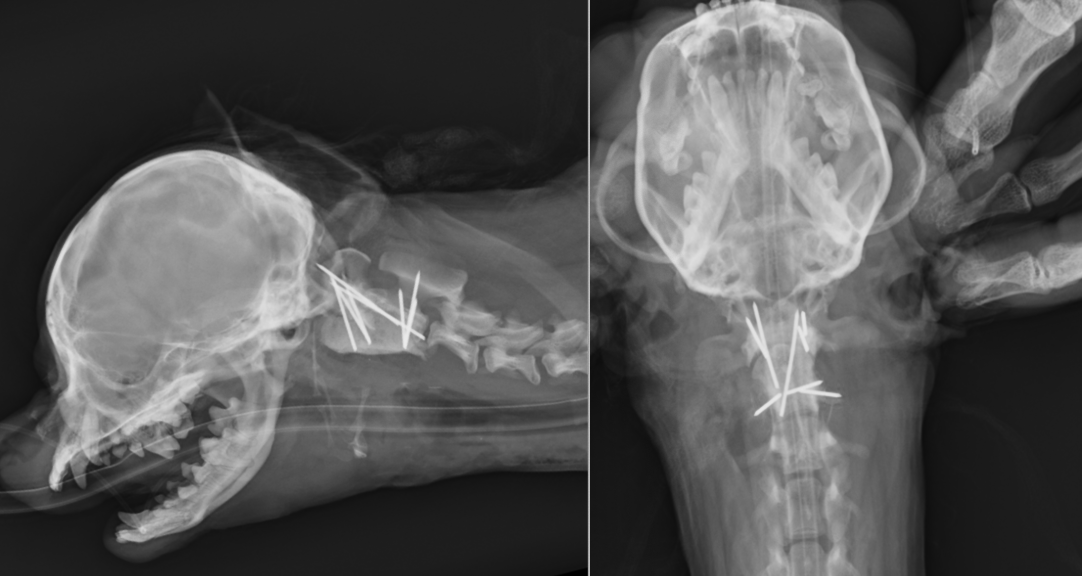

次の症例は先程の症例よりも重症で、手術時には自力での歩行が困難で、やっとおすわりができるかできないかという状態でした。また手術時の体重が2kgしかなかったので、難易度は高い手術となりました。

MRIでは重度に脊髄が圧迫されており、環軸椎の部分で脊髄が重度に狭窄しているのが分かります。

手術では骨が小さかったため、どうしても細いピンを使わざるを得ず、さらに術後にMRIを撮影する可能性を考えチタン製のものを使用しました。そのため、強度を上げるため通常よりも本数を増やし8本のピンを刺入しました。

それらのピンを切ってから海綿骨を移植して骨セメントを入れたところになります。熱が発生するため積極的に冷やしています。

術後レントゲンです。8本のピンが刺入されているのが分かります。術後からとても経過はよく、1週間後には歩行可能となり、3ヶ月経過現在元気に歩き回っています。